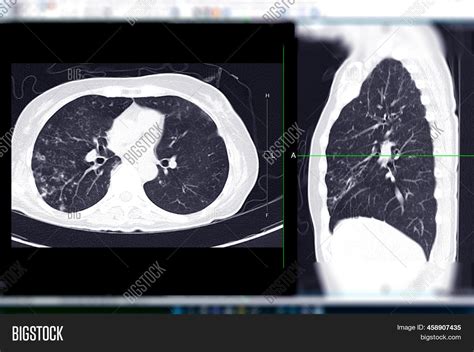

A Ct Scan En Español is a diagnostic imaging procedure that uses a combination of X-rays and computer technology to produce cross-sectional images of the body. These images provide detailed views of organs, bones, and other internal structures, allowing healthcare providers to detect abnormalities, injuries, and diseases with high accuracy.

• Scanning: The patient lies on a table that slides into the CT scanner, a large, doughnut-shaped machine. The scanner rotates around the body, taking multiple X-ray images from different angles.

• Image Processing: The images are then processed by a computer to create detailed cross-sectional views of the body.

Lung Nodules CT scans can identify small nodules in the lungs, which may indicate early-stage lung cancer.